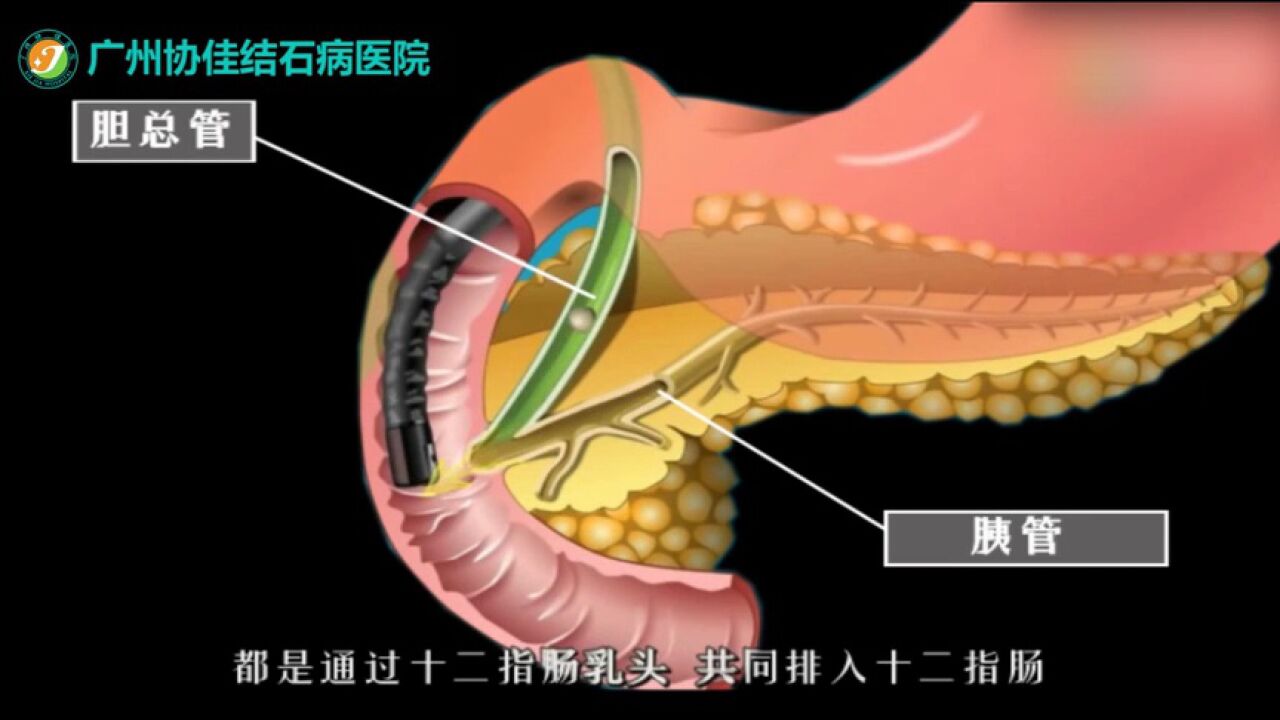

次に、これらの切り込みの 1 つからカテーテルを挿入し、胆嚢と総胆管を接続する胆嚢管にカテーテルを配置します。このカテーテルを使用して、特殊な種類の染料を管内に注入します。この色素を使用すると、外科医は胆嚢を切除して胆石の有無を確認しながら、モニターで胆管を観察できるようになります。

IOC が胆石があることを示した場合、外科医は手術中に胆石を除去するか、治療のための次回の予約をするよう指示することがあります。